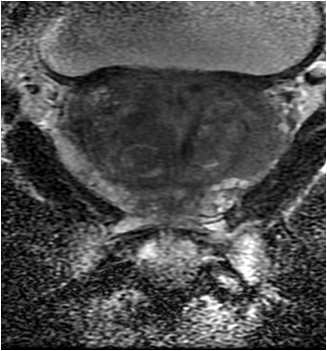

Figure 1 is a 48 year old male with a PSA of 5.23 ng/ml and biopsy proven prostate carcinoma of Gleason score 10 (5.5).

Figure 1a: Diffusion MRI scan showing the tumor (white arrow)